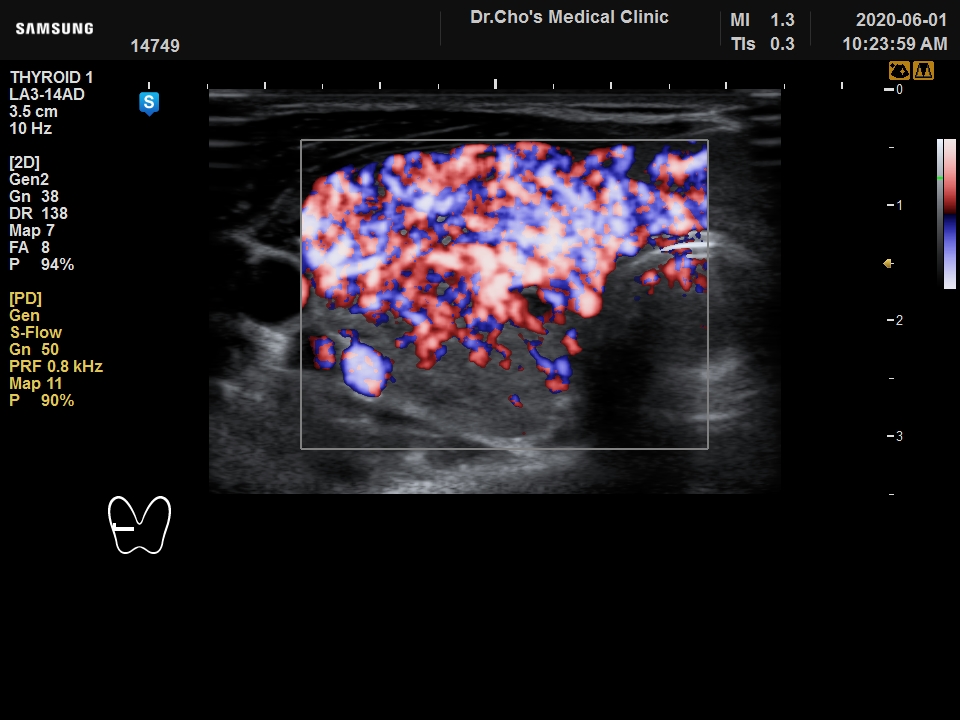

ÃÊÀ½ÆÄ°¶·¯¸®

°©»ó¼± À¯...

±×·¹À̺꽺...